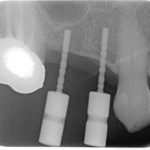

Autotrapianto di ottavo incluso a sostituzione di un settimo irrimediabilmente compromesso: case report

I trapianti dentali sono un capitolo...